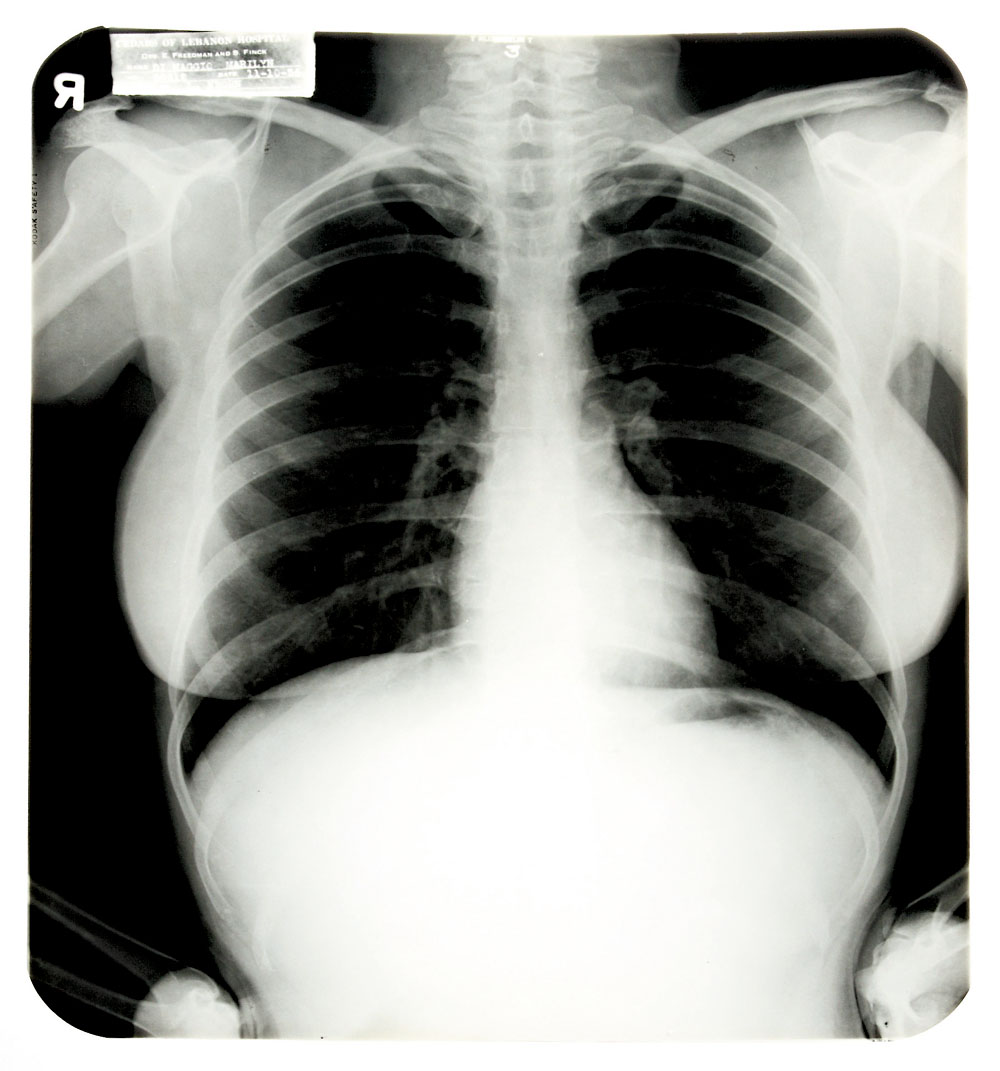

已故性感女神瑪麗蓮夢露的各類遺物有着無盡的市場。在高價拍出她的香水,台詞冊等物品之後,她的胸部X光片也成了買家熱捧的商品。據美國媒體報道,當地時間27日,美國內華達州拉斯維加斯舉辦的荷里活傳奇拍賣會上,瑪麗蓮夢露1954年在醫院拍攝的三張胸部X光片以4.5萬美元(約35萬港元)的高價拍出。